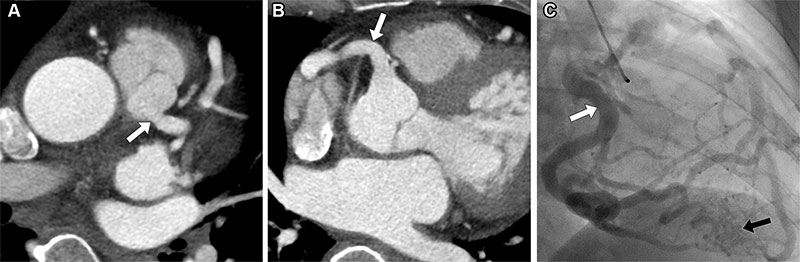

Anomalous left coronary artery from the pulmonary artery in a 50-year-old woman who presented to the emergency department with chest pain. (A, B) Axial intravenous contrast-enhanced chest CT images show an anomalous origin of the left main coronary artery arising from the main pulmonary artery (arrow in A) with coronary dilatation and a dilated right coronary artery (arrow in B) due to collateral vessel supply to the myocardial territory by the left main coronary artery. (C) Invasive catheter coronary angiogram acquired one week later shows tor[1]tuosity and dilatation of the right coronary artery (white arrow) giving rise to collateral vessels that supply the left main coronary artery territory (black arrow).